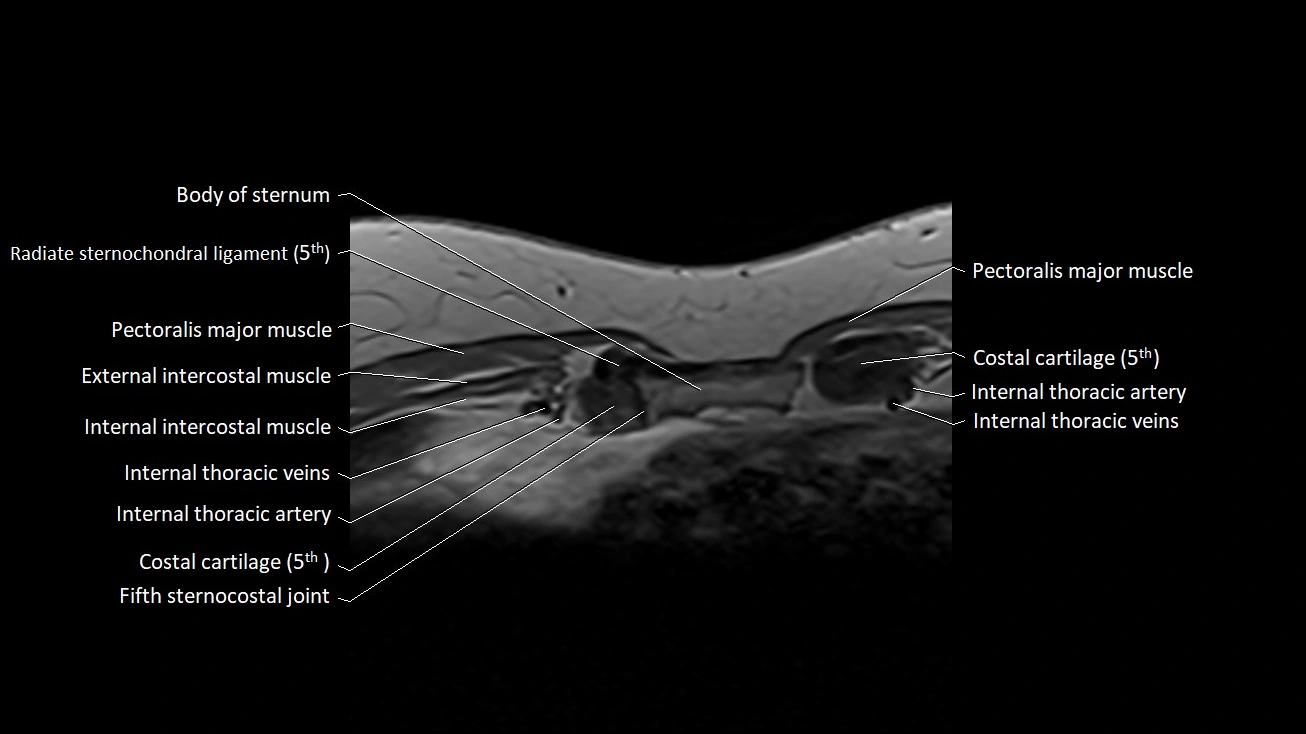

MRI images

image